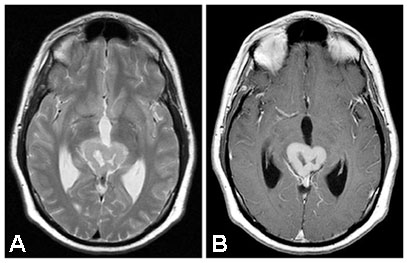

Figure 3 |

Fig. 3 (October, 2002)

(A) T2 (B) T1-Gado |